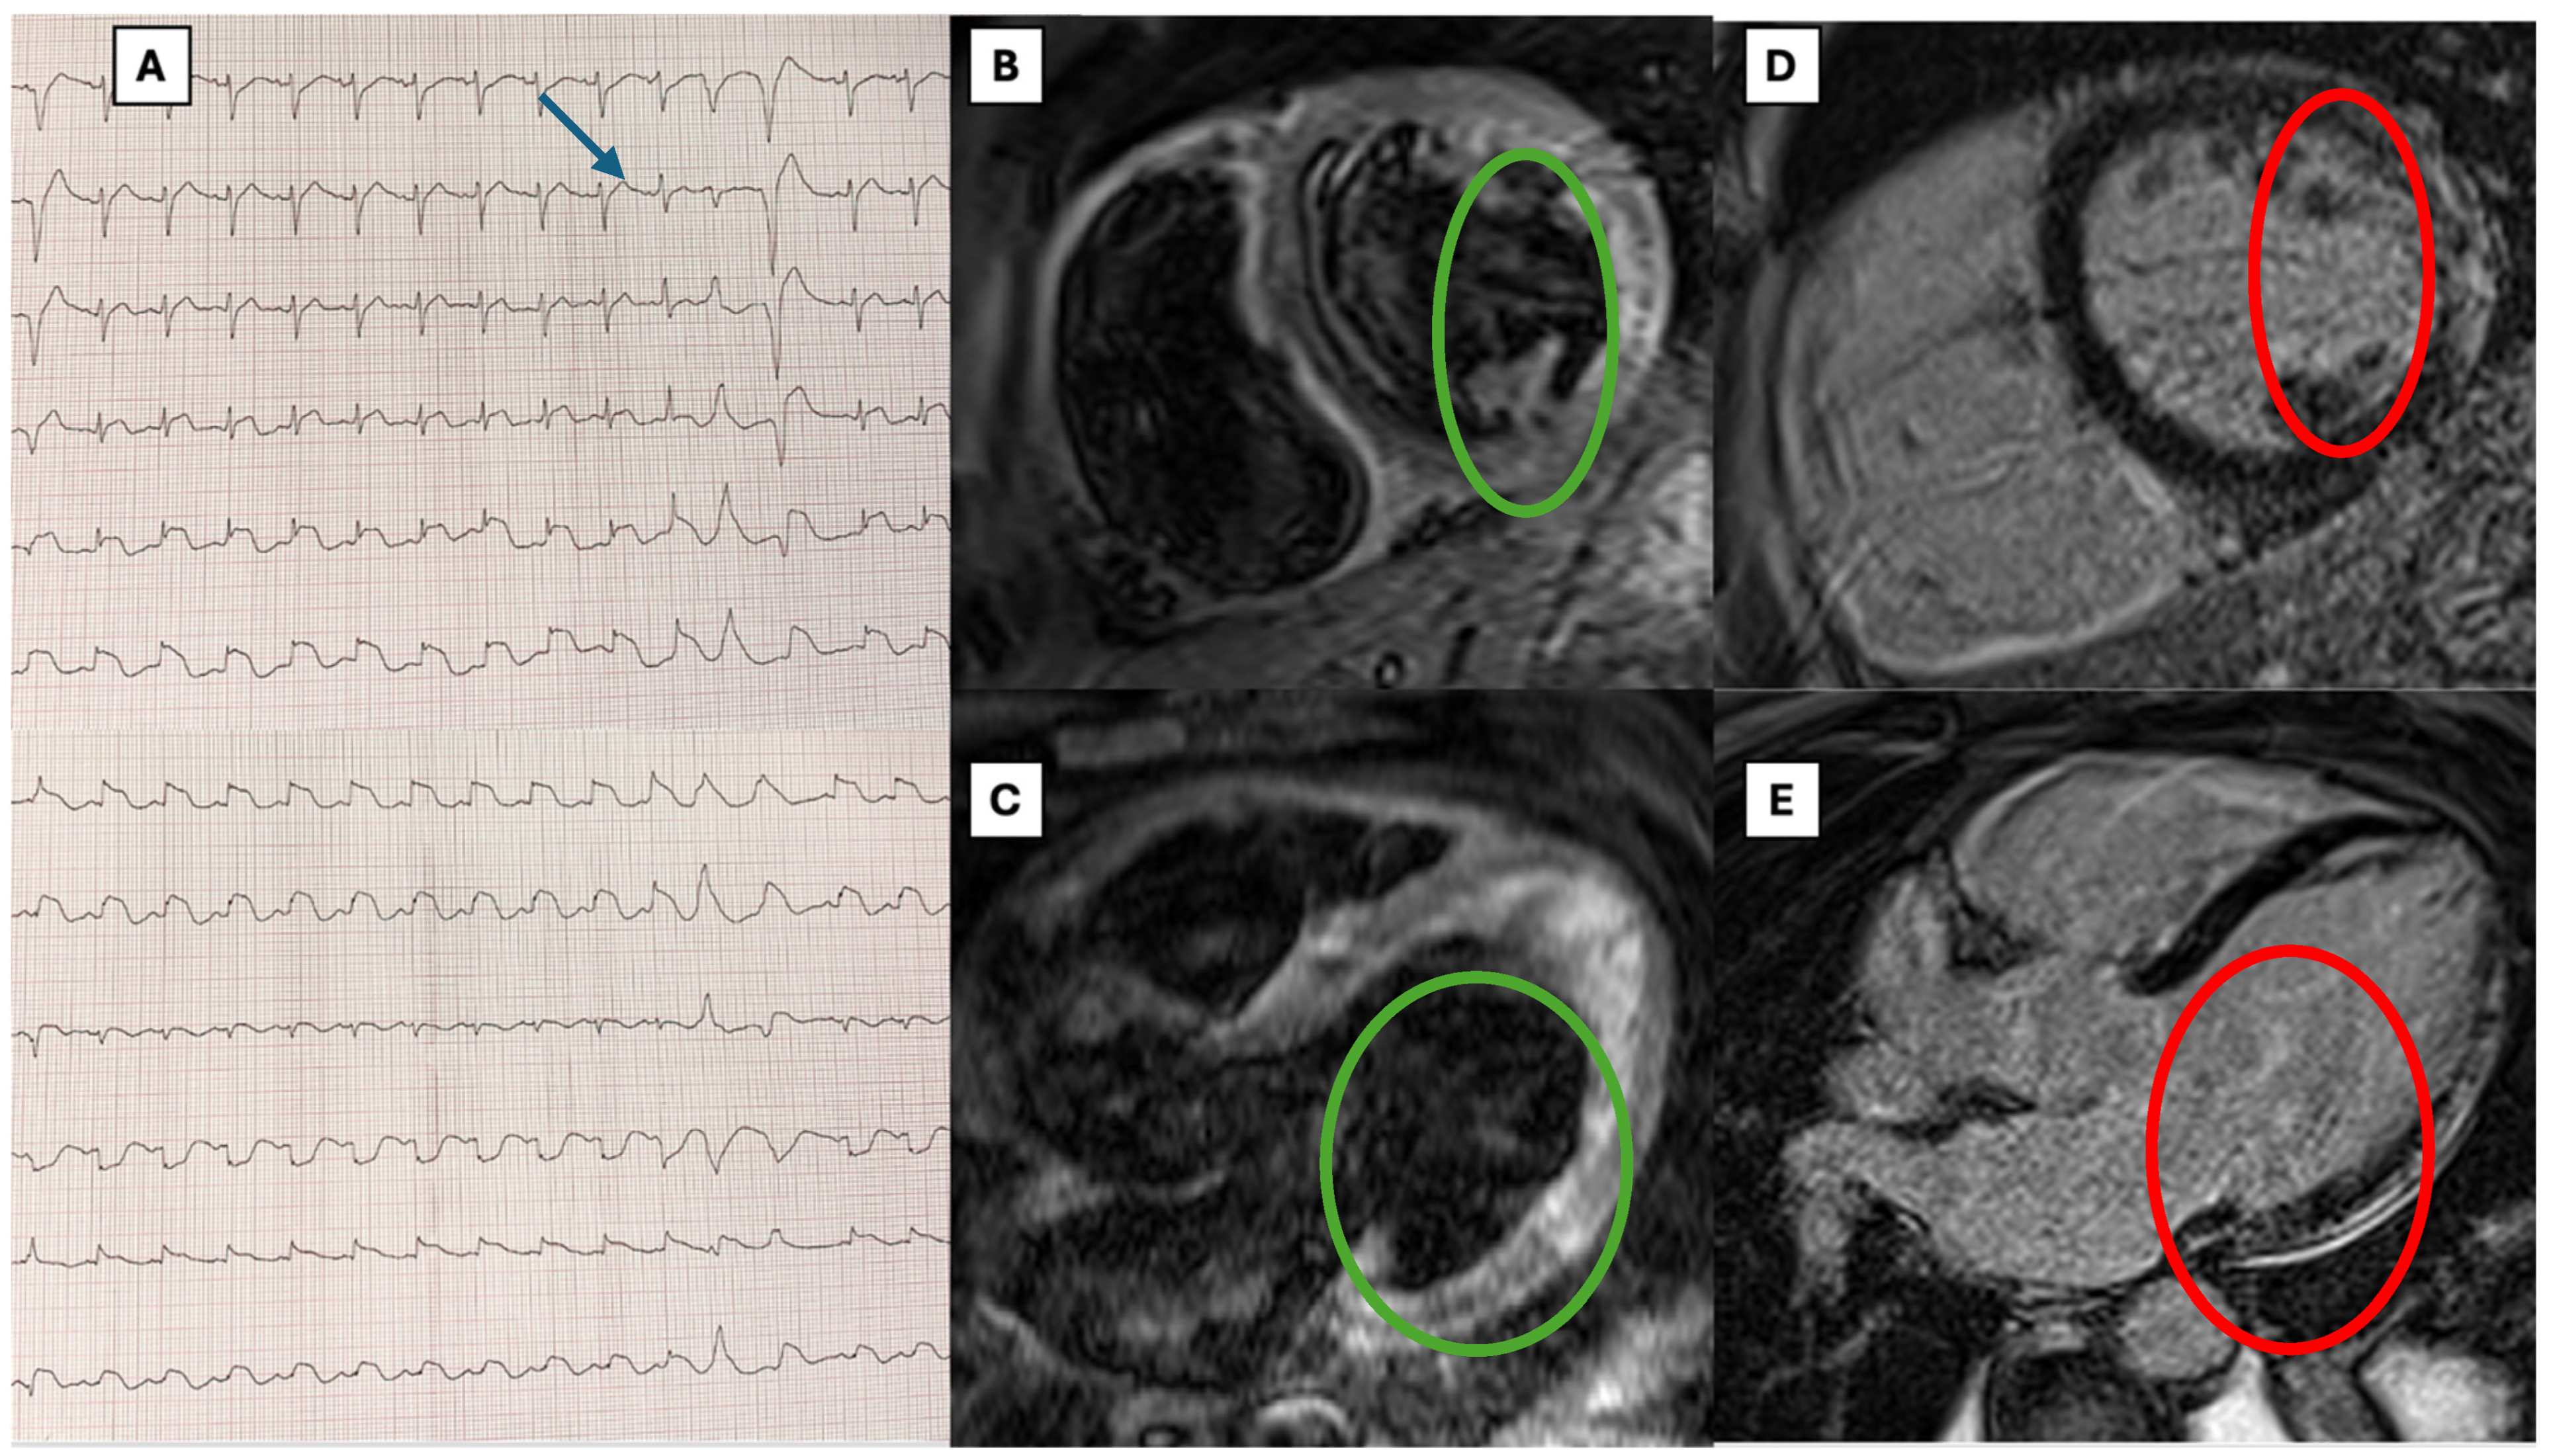

| Index case | 47 | M | DM | Aromatic hydrocarbons | Dyspnea | Diffuse ST elevation, NSVTs, and one episode of VF | 1.6 ng/mL | Severe biventricular dysfunction and right ventricular dilatation (LV EF 26%, RV FAC 16%, RV EDA 16 cm2/m2) | Neg | Edema and subepicardial LGE on lateral and inferior wall of LV; T1 mapping and extracellular volume increased | Acute lymphocytic myocarditis; molecular analysis revealed positive B19V transcriptional activity with significant viral load (>500 copies/μg) | Antiarrhythmic therapy with amiodarone and lidocaine; PSGB, vasoactive therapy with norepinephrine; inotropic support with levosimendan and dobutamine; heart failure treatment: ARNI, betablocker, MRA, and iSGLT2 | At 3-month follow-up: class I NHYA; echo with normalization of LVEF; no malignant arrhythmias at 24 h Holter ECG | no |